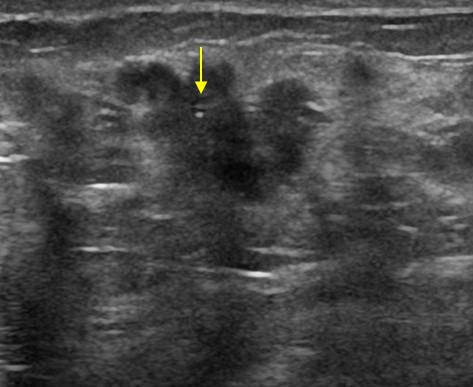

Ung thư vú

Ung thư vú - Ảnh 5

» Thông tin: Nữ giới – 52 tuổi.

» Lâm sàng: Khối tuyến vú.